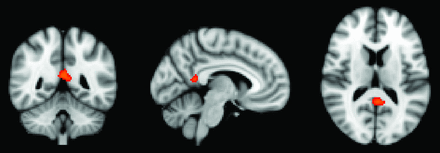

In a first step, we performed a voxelwise analysis across the entire brain. The posterior cingulate cortex demonstrated a significant difference between APOE*E3 > APOE*E4 for the dCON group (Fig 1).

Whole-brain voxel-based morphometry analysis demonstrating higher GM density for the comparison of APOE*E3 > APOE*E4 in the posterior cingulate cortex. P < .05 corrected.